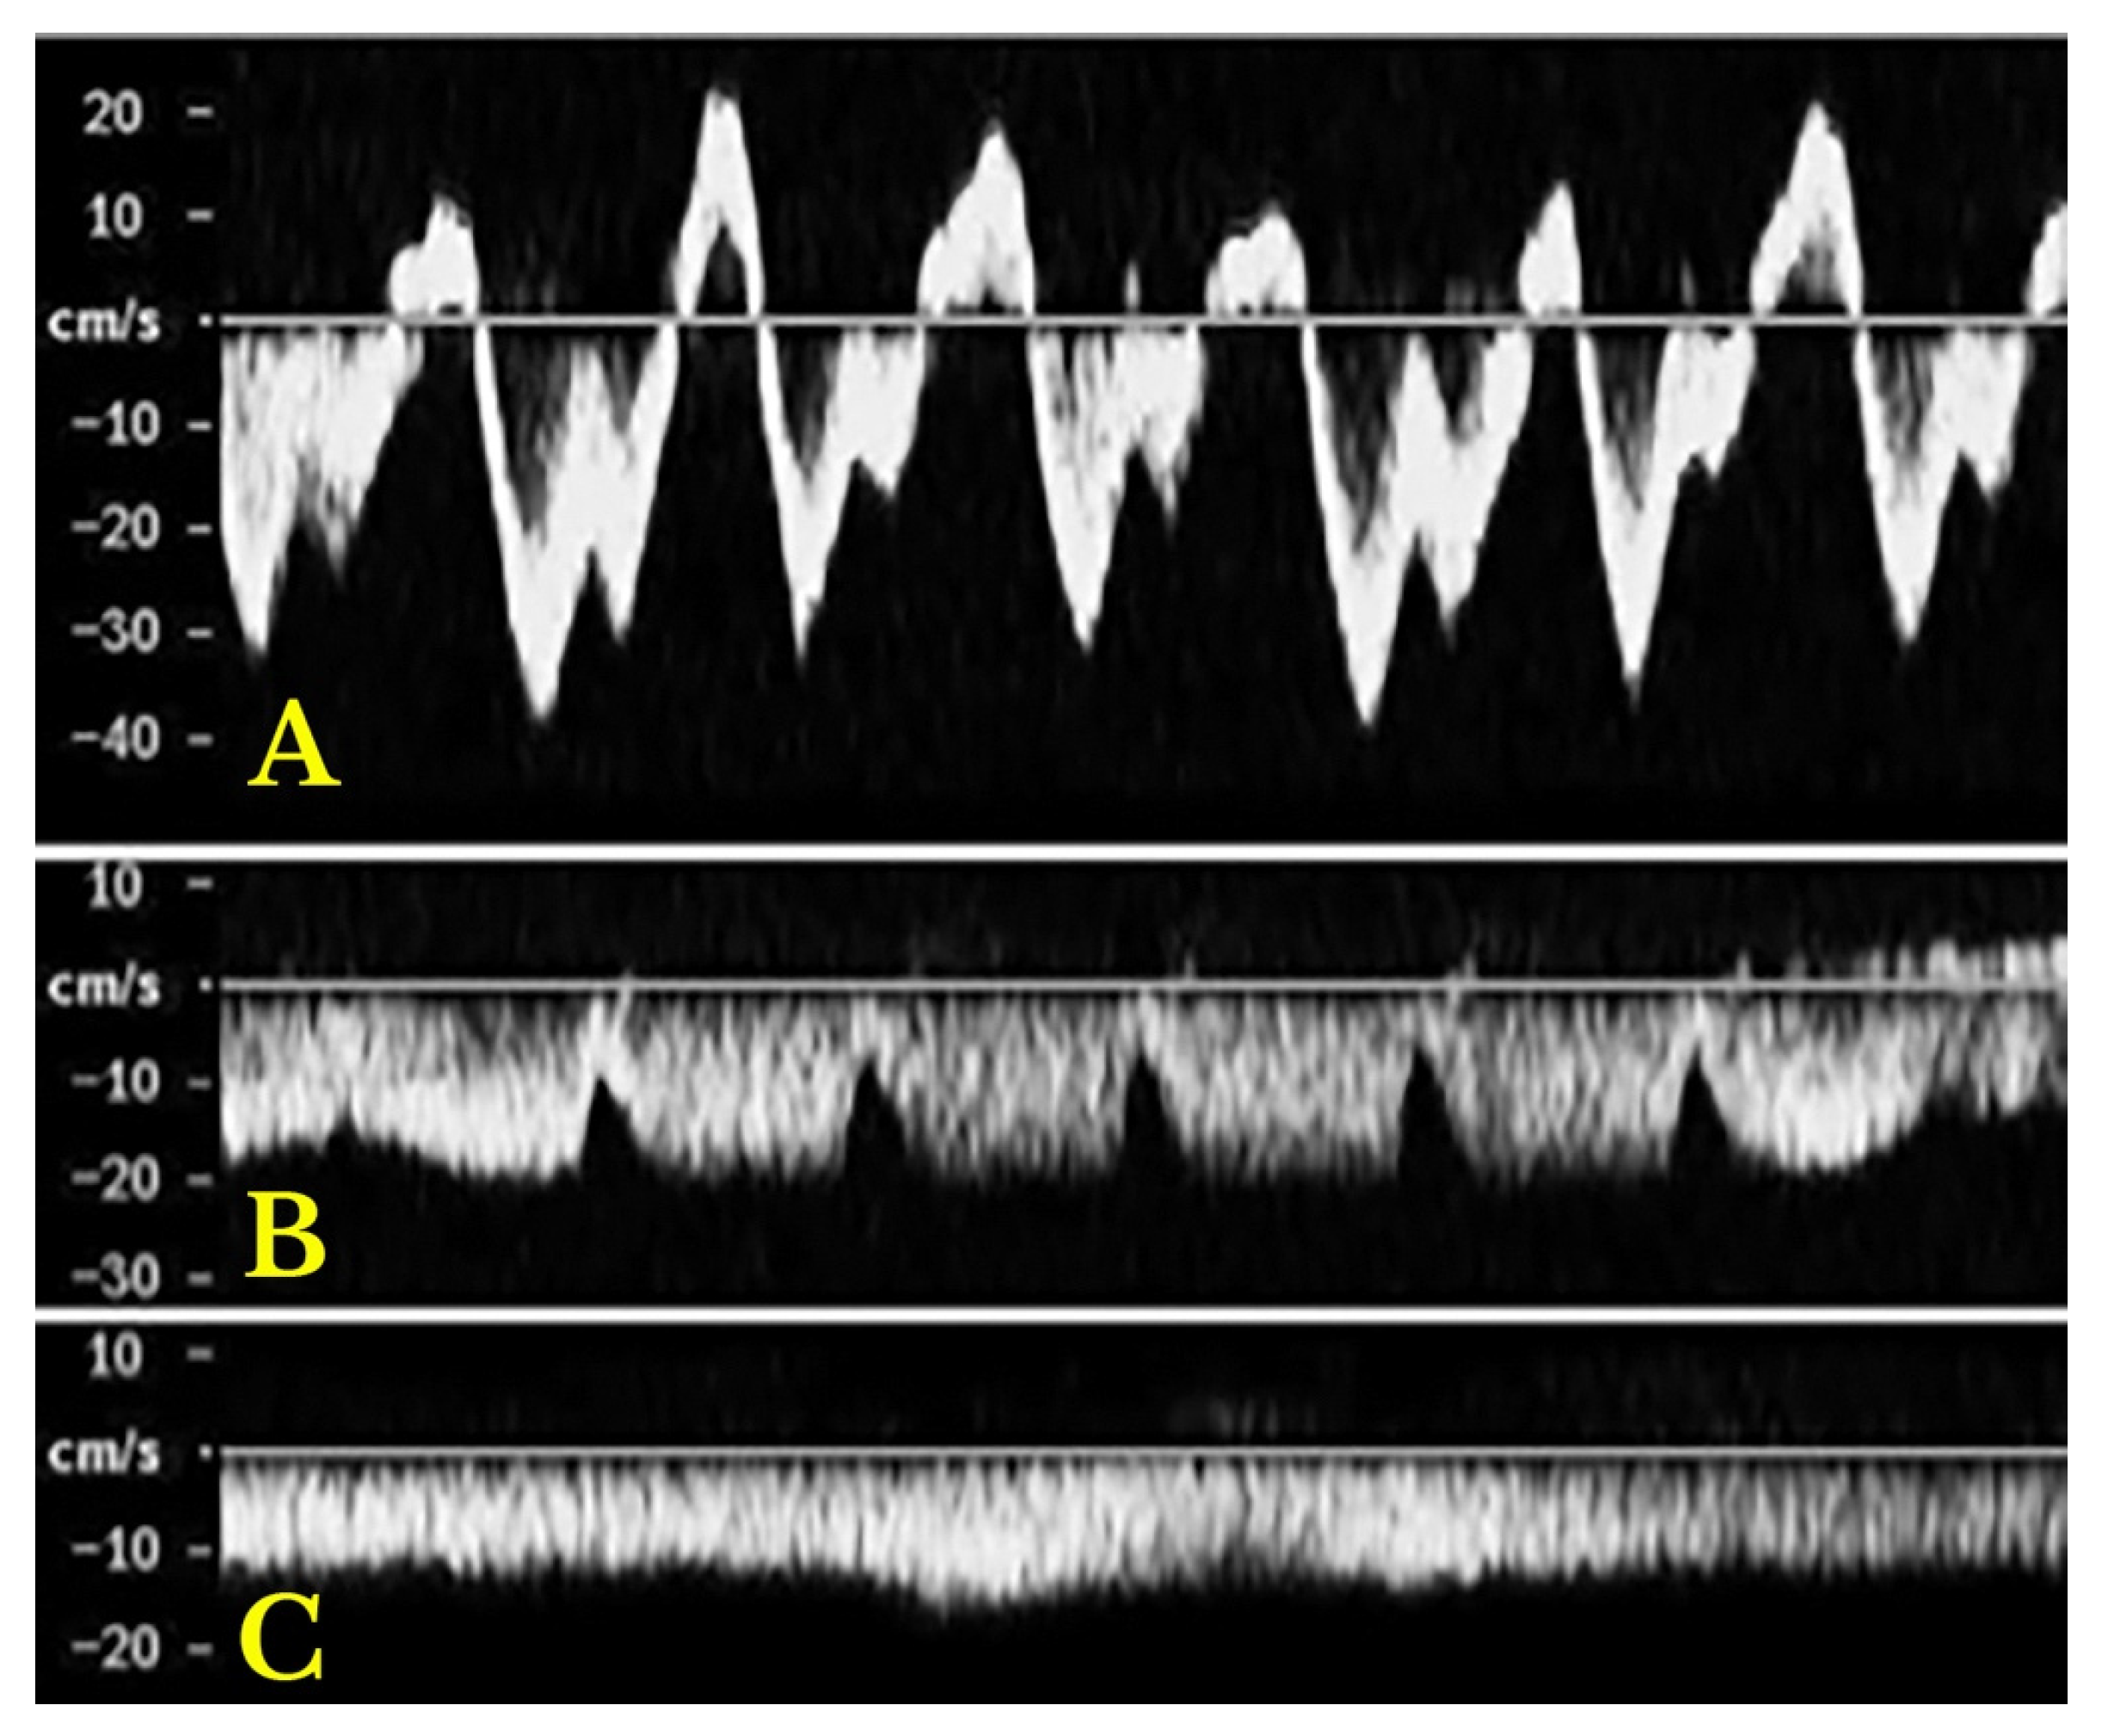

- Intra-Renal Vein Doppler: Similar to the portal vein, intra-renal veins show continuous flow under normal conditions, but congestion leads to a pulsatile pattern. This can manifest as a biphasic pattern in moderate congestion and a monophasic pattern in severe cases [114]. Altered intra-renal flow is associated with poor outcomes in heart failure and pulmonary hypertension patients [56,114].

- Hepatofugal (Retrograde) Flow: Hepatofugal flow happens when the pressure in the portal vein exceeds that of the liver, causing flow to reverse and appear below the baseline. This is another indicator of portal hypertension, which can be caused by various conditions, including cirrhosis, right-sided heart failure and other portal vein obstructions [107] (Figure 9).Figure 9. (A) Increased pulsatility due to arteriovenous shunting in a case of hereditary haemorrhagic telangiectasia; (B) Reduced Portal Flow in a case of cirrhosis (C) Hepatofugal Flow of Portal Vein is a late sign of Portal Hypertension. It happens when the pressure in the portal vein exceeds that of the liver, causing flow to reverse and appear below the baseline. This is another indicator of portal hypertension, which can be caused by various conditions, including cirrhosis, right-sided heart failure and other portal vein obstructions.Figure 9. (A) Increased pulsatility due to arteriovenous shunting in a case of hereditary haemorrhagic telangiectasia; (B) Reduced Portal Flow in a case of cirrhosis (C) Hepatofugal Flow of Portal Vein is a late sign of Portal Hypertension. It happens when the pressure in the portal vein exceeds that of the liver, causing flow to reverse and appear below the baseline. This is another indicator of portal hypertension, which can be caused by various conditions, including cirrhosis, right-sided heart failure and other portal vein obstructions.